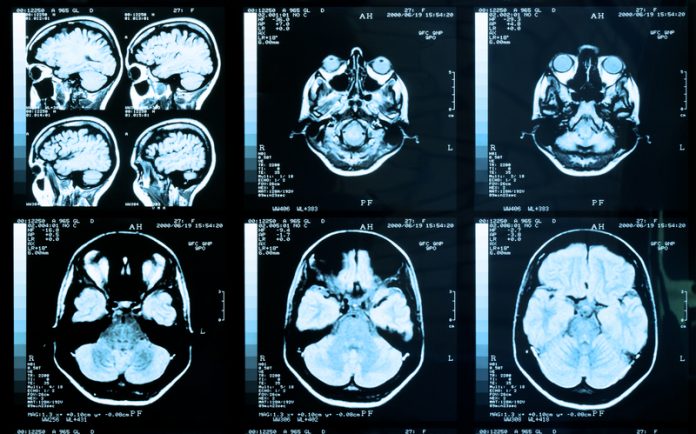

A normal HTT protein has between 7 and 35 glutamines. Increased number of glutamine repeats changes the property of the protein and renders it toxic to cells. The HTT protein is present throughout the body and throughout life. However, mutant HTT is toxic to select cells. Postmortem examination of the brains of affected individuals shows massive cell loss in certain parts of the brain, leaving other cells and tissues intact. This indicates that some neurons are particularly sensitive to the toxic effects of mutant HTT.

However, misfolded proteins can accumulate over time and form irreversible aggregates that impair cellular homeostasis. These aggregates are a hallmark of many neurodegenerative diseases. They are found in postmortem brain tissues of affected individuals. Age-associated diseases such as Alzheimer’s disease, are linked to protein misfolding. HD is also considered a protein misfolding disease although many other mechanisms are thought to play a role in the disease pathogenesis.